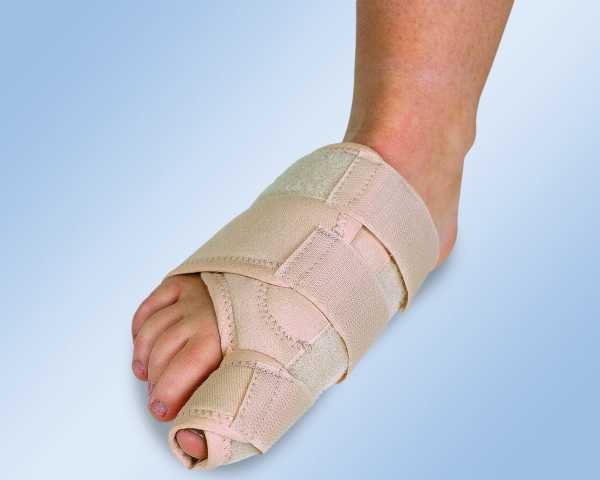

Ортопедические приспособления

В качестве консервативных мер, направленных на выправление деформированной стопы, рекомендуют использовать специальные ортопедические приспособления. К таковым относят:

- стяжки;

- стельки;

- ночной корректор;

- ортопедическая шина.

Лечебные стельки изготавливают для каждого пациента индивидуально. Они направлены на снятие основной нагрузки с больного сустава и на возвращение стопе амортизирующих свойств.

Для выравнивания фаланги пальцев и уменьшения угла деформации применяют специальные супинаторы и перегородки. Обычно используют ночной корректор, который позволяет удержать большой палец в правильном положении.

Ночной бандаж

Для постоянного ношения изобретены ортопедические шины, которые позволяют зафиксировать смещенный палец в неподвижном состоянии и со временем выравнивают форму стопы.

Ортопедическая шина, которую можно носить постоянно